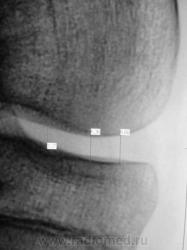

Женщина. 61 год. Вес 120 кг. Жалобы на боли и "хруст" в коленях. Рентгенологически - двусторонний артроз 3-й степени с наличием "вакуум-феноменов" в области внутренних менисков, большей выражености слева.

Сравнительная характеристика - в положении стоя наружные суставные щели гораздо шире, Х-образные конечности, ось нагрузки на внутренние отделы; в положении лежа уменьшаются. В положении лежа"соскальзывание" голеней наружу меньше. Внутренние суставные щели в положении лежа едва шире, очевидно сказывается резкое истончение мениска и хрящей со значительной потерей эластичности. Метрические показатели пока не оценивал. КАк поступить - мерить? тогда как лучше, дабы стандартизировать подход?

Смысл в затеяном эксперименте - разница высоты (ширины) суставных щелей коленного сустава в положении стоя и лежа в норме и при патологических состояниях, хотите - присоединяйтесь.